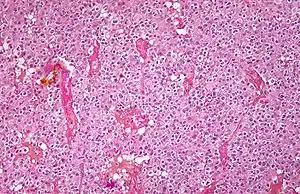

Micrograph of an oligodendroglioma showing the characteristic branching, small, chicken wire-like blood vessels and fried egg-like cells, with clear cytoplasm and well-defined cell borders. H&E stain.

Low magnification micrograph of an oligodendroglioma showing the characteristic, small, branching, chicken wire-like blood vessels. H&E stain.

Oligodendrogliomas cannot currently be differentiated from other brain lesions solely by their clinical or radiographic appearance. As such, a brain biopsy is the only method of definitive diagnosis. Oligodendrogliomas recapitulate the appearance of the normal resident oligodendroglia of the brain. (Their name derives from the Greek roots 'oligo' meaning " few" and 'dendro' meaning "trees".) They are generally composed of cells with small to slightly enlarged round nuclei with dark, compact nuclei and a small amount of eosinophilic cytoplasm. They are often referred to as "fried egg" cells due to their histologic appearance. They appear as a monotonous population of mildly enlarged round cells infiltrating normal brain parenchyma and producing vague nodules. Although the tumor may appear to be vaguely circumscribed, it is by definition a diffusely infiltrating tumor.

Classically they tend to have a vasculature of finely branching capillaries that may take on a "chicken wire" appearance. When invading grey matter structures such as cortex, the neoplastic oligodendrocytes tend to cluster around neurons exhibiting a phenomenon referred to as "perineuronal satellitosis". Oligodendrogliomas may invade preferentially around vessels or under the pial surface of the brain.